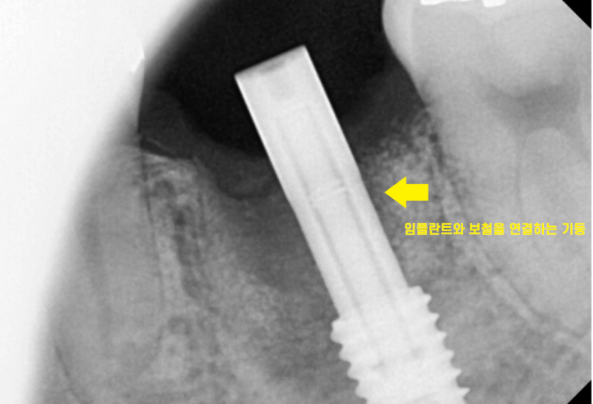

시간이 흘러 기계로 얼마나 내 뼈와 잘 붙었는지 수치를 측정하고

이제 잘 붙었다면 뽄을 떠주는 단계입니다.

뽄을 뜨는 것은 머리 부분에 해당하는

씹을 수 있는 무언가를 만들어주기 위해서입니다.

보철 제작을 완료하면

구강 내에 접착을 시행합니다.